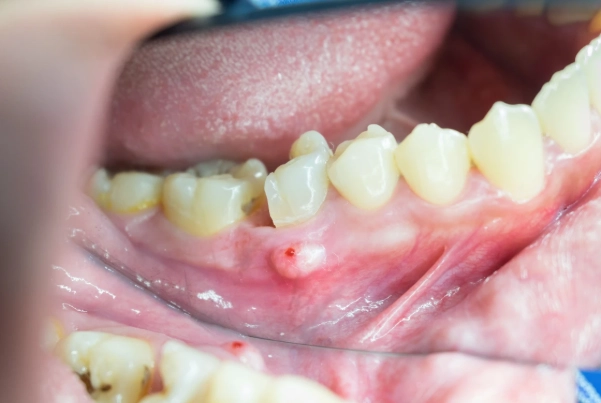

- That "pimple on the gum" (fistula): It might drain a bad-tasting, salty fluid, providing temporary relief.